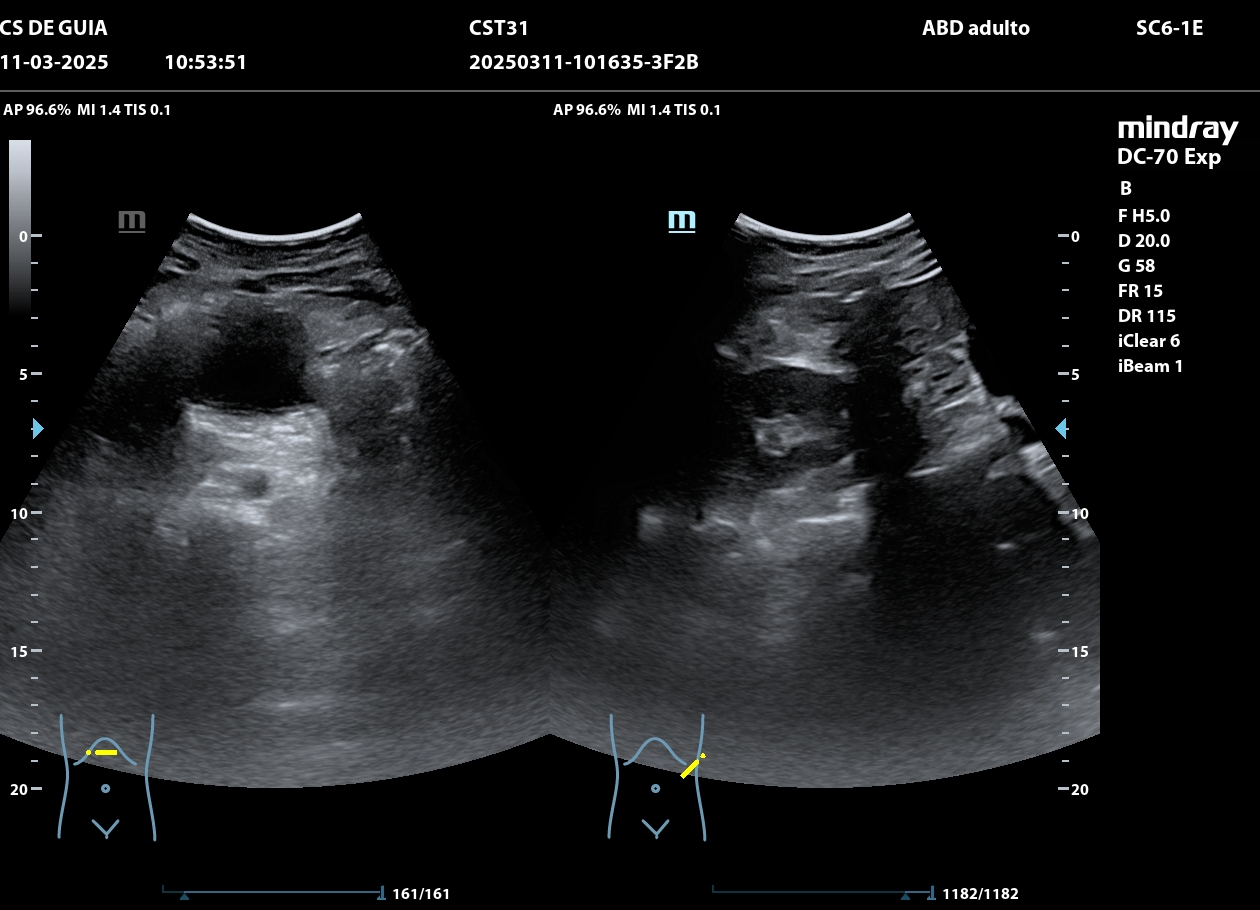

Se realiza ecografía clínica en consulta. Se observa lesión quística sin captación Doppler desde hipogastrio hasta mesogastrio compatible con cistoadenoma de ovarios (no se puede apreciar debido al gran tamaño si de anejo izquierdo o derecho), con útero sin alteraciones, no hidronefrosis.

La paciente fue derivada al Hospital donde tras realizar nuevamente ecografía: Útero en anteversión de bordes regulares. Endometrio lineal. Anejo derecho normal. A nivel de anejo izquierdo se objetiva formación que escapa alcance de sonda TV por lo que se completa examen vía ECO ABD. Formación multilocular de contenido sólido de baja densidad de 225*108*157 mm, con > 10 lóculos, componente sólido a expensas de confluencia de tabiques de 26 mm de diámetro máximo contenido de bajo nivel, sombra acústica presente. Doppler score 2-3 en tabiques. No líquido libre.